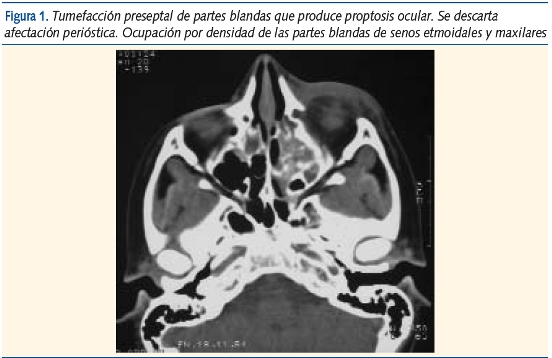

Los hallazgos clínicos al ingreso fueron: fiebre (100%), edema palpebral (100%), hiperemia y exudación ocular (50%) y dolor (26%). Sólo un paciente fue diagnosticado en el ingreso de posible celulitis orbitaria. Tras aplicar una técnica de imagen (TC), el diagnóstico fue de celulitis periorbitaria (figura 1).

Se aplicó una técnica de imagen en 27 pacientes: 22 radiografías de senos paranasales, 4 TC y 1 ortopantomografía. La mediana de edad del grupo en el que se realizó la técnica de imagen fue de 60 meses (14-171 meses). Dentro de este grupo se objetivaron 19 casos de sinusitis asociada. En todos ellos se encontraba afectado el seno maxilar, mientras que los senos frontales y etmoidales sólo estaban afectados en 2 y 8 pacientes respectivamente. La mediana de edad en la que se objetivó una afectación sinusal fue de 69 meses (21-171 meses).